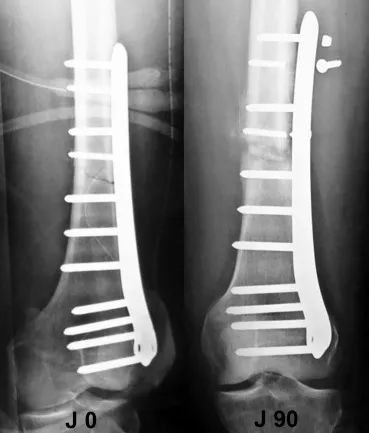

что также связано с слишком жесткой конструкцией. Это приводит к тому, что один конец пластины выдвигается «целым» и заживление не достигается (рис. 8).

Рисунок 8. Вторичный отказ слишком жесткой и несбалансированной конструкции: слишком много стопорных винтов было использовано дистально, а проксимальная соединительная пластина была недостаточно длинной.